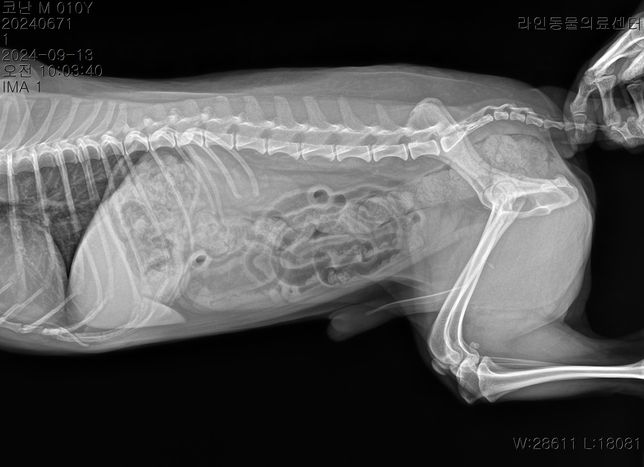

- 반려동물 건강반려동물Q. 강아지 허리 디스크 ct 사진 첨부합니다.. 재질문합니다..한달에 한번 주기로 깨갱 거리면서 특히나 혼자 붕가붕가하고 나서 그러는데요허리 디스크가 어느정도 상태인지 그리고 붕가붕가를 평생 못하게해야하는건지.. 알려주시면 감사하겠습니다....T4-6 vertebrae의 Rt. caudal articular process의 defect 확인됩니다. (→)• T13-L1 vertebrae의 IVDS(intervertebral disc space)가 주변에 비해 좁게 확인됩니다.T13-L1 vertebrae의 IVDS가 주변에 비해 좁게 확인되어 IVDD 가능성고려됩니다.

- 반려동물 건강반려동물Q. 선생님 저희 강아지 허리디스크가 어느정도인가요?한달에 한번 주기로 깨갱 거리면서 특히나 혼자 붕가붕가하고 나서 그러는데요 허리 디스크가 어느정도 상태인지 그리고 붕가붕가를 평생 못하게해야하는건지.. 알려주시면 감사하겠습니다....